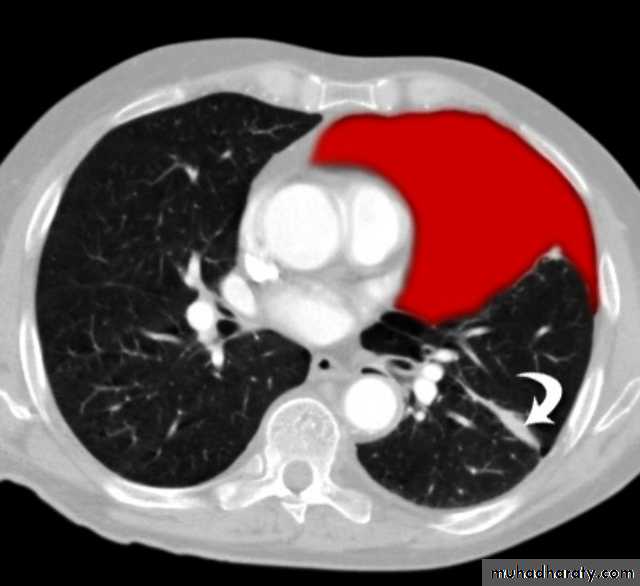

Pancreatitis

Patient present with abdominal pain , vomiting with or without jaundice , increase amylase level

CT finding

Enlargement of the pancreas focal or generalized increase in size .

Hypo density within the pancreas focal or generalized due to the edema .

Peri pancreatic fluid collection & edema around the pancreas .

The fluid around the pancreas if persist more than 6 w become encysted leading to the pancreatic pseudo cyst any area could be affected .

Edema of the wall of the stomach .

CT Scane